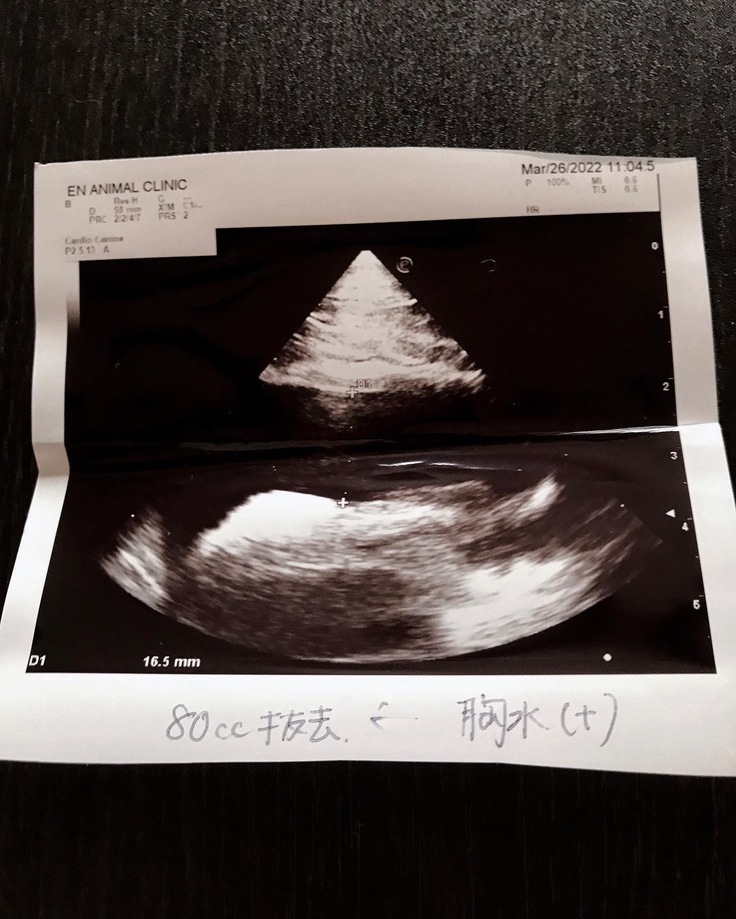

【エコー画像、胸水抜去量】

3月29日

外注検査結果の連絡があり

FIP混合タイプ陽性の診断を受けました。

※えんアニマルクリニックさんには

掲載許諾をいただいております。